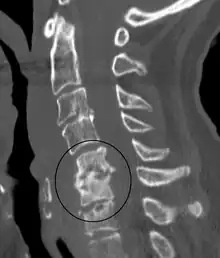

Dentro de las pruebas de laboratorio, se da un incremento del recuento de glóbulos blancos en el 13-60% de los casos. Asimismo, la tasa de sedimentación eritrocítica y los niveles de proteína C reactiva se hallan elevados en más del 90% de los casos. El gold standard para el diagnóstico de discitis es el empleo de biopsia guiada a través de tomografía axial computerizada (TAC) y la realización de un hemocultivo, dando resultado positivo en un 70-90% de los casos. Los cultivos son esenciales a la hora de determinar o descartar su posible origen bacteriano.[4]

En cuanto a las pruebas radiológicas, la radiografía arroja una sensibilidad del 82% y una especificidad del 57%. Los primeros signos radiográficos incluyen la pérdida de la lordosis lumbar, el estrechamiento del espacio intervertebral e irregularidades en la carilla articular de los cuerpos intervertebrales. La resonancia magnética nuclear tiende a arrojar resultados muy precisos, con una sensibilidad y especificidad del 95% en ambos casos.[4]